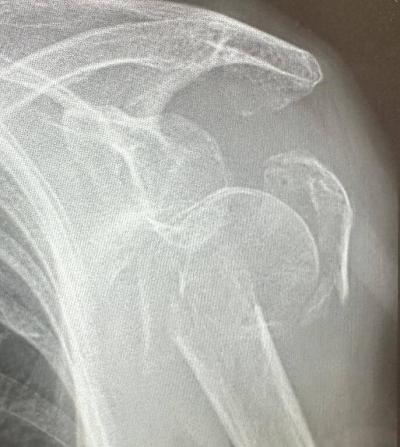

Een goed resultaat schouderbreuk bij 95 jaar Lees meer

schouderbreuk bij 95 jaar schouderbreuk bij 95 jaar